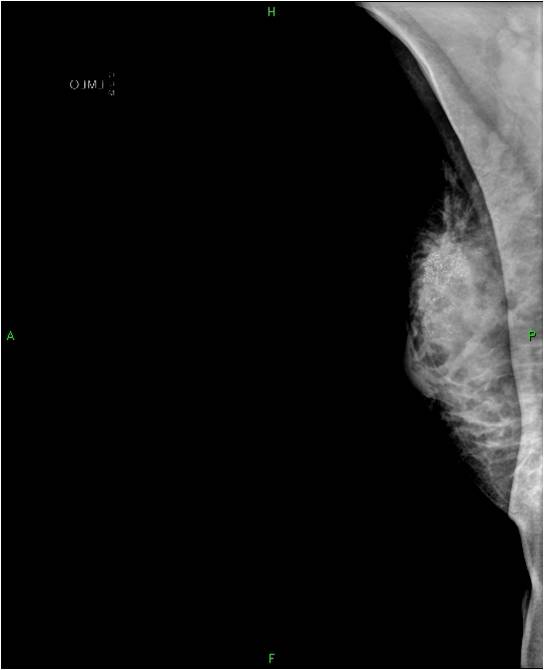

2. Digital mammography has displaced the analogue technic for today almost everywhere: (pictures 1,2,3) phosphorous plate or direct digital methods. For breast imaging the latter is the method of choice. Phases of image production separate. The image is produced on the detectors, but appears on the high resolution monitor and can be stored as a digital data set at various storage mediums (e.g.: CD, hard disk drives).

Image

Picture 1.

Picture 2.

Picture 3.